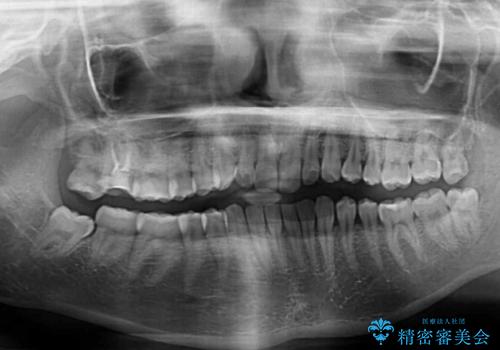

- 根管治療を行ったままの奥歯と、矯正治療の後戻りを気にして来院された患者様です。

根管治療された歯に症状はなく、オールセラミッククラウンにて補綴治療を行うこととしました。

クラウンはよりよい咬み合わせで装着したいため、インビザラインを1セット使用して概ね歯列を整えた時点で補綴治療を行い、その後仕上げの矯正治療を行いました。